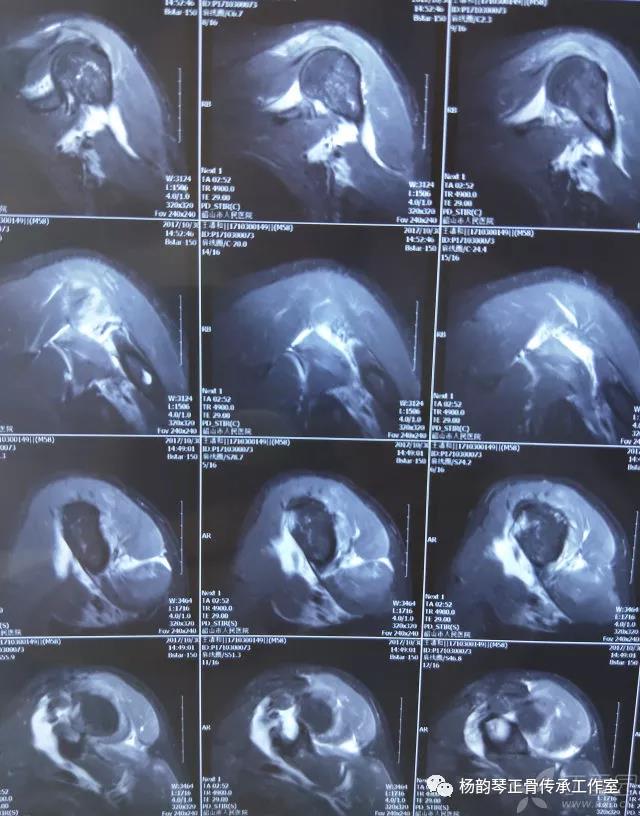

简要病史:骑摩托车跌倒致左肩部肿痛,活动受限,就诊于当地医院,拍片及磁共振检查后诊断为肩袖损伤及肩关节半脱位,予以悬吊固定,因症状缓解不明显就诊于我院。外院拍片情况如下:

应该说是一个典型的“灯泡征”影像,但是并未引起注意。

当地接诊医生应该说还是很负责的,同时拍了健侧片对比:

影像科报告,骨科医生光看报告行吗?

磁共振检查也完善了,还是报了个肩关节半脱位……影像科已经把坑挖好了……

接诊医生直接跳坑里了